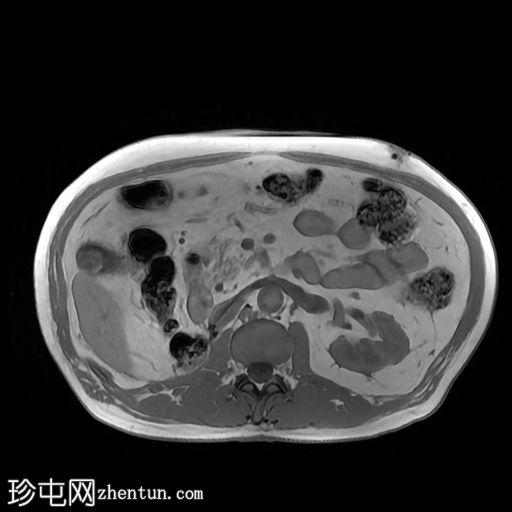

高危肾细胞癌分期CT检查。

冠状位

行CT检查以进行分期。已知肾细胞癌。已行右侧根治性肾切除术和左侧肾上腺切除术。胆囊内可见强化物质,提示胆囊底部血管受累。骨窗下胆囊内未见钙化灶。影像表现提示胆囊转移。